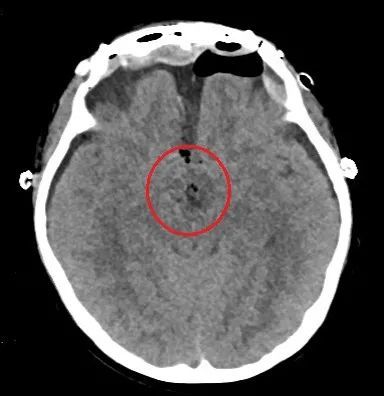

术前头部CT和磁共振检查显示:鞍区肿瘤(红圈内)比乒乓球还大,压迫周围重要的神经和血管。

入院后进一步检查发现,肿瘤约为4.5×4.4×4.6cm,比乒乓球还大,周围遍布颈内动脉、视神经、三脑室底、海绵窦、垂体、垂体柄等重要的神经和血管。